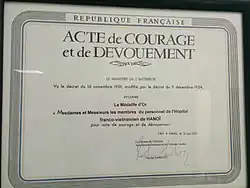

Le syndrome respiratoire aigu sévère (SRAS) est une maladie infectieuse des poumons (pneumonie aiguë) due à un coronavirus, le SARS-CoV, apparu pour la première fois en Chine en , qui a provoqué une épidémie à partir de dans 29 pays, infecté plus de 8 000 personnes et causé la mort de 916 personnes. La maladie s'est manifestée jusqu'en [1]. En 2003, le virus apparaît à Hanoï, au Viêt Nam, véhiculé par un homme d'affaires chinois qui avait croisé le patient zéro de Hong Kong. Il est admis à l'Hôpital français de Hanoi le , où il infecte au moins 38 membres du personnel. Il est évacué à Hong Kong, où il meurt le . Un spécialiste des maladies infectieuses de l'Organisation mondiale de la santé, Carlo Urbani, examine le patient et observe la très grande contagiosité, la nouveauté et la dangerosité de la maladie. Il avertit immédiatement l'OMS, qui déclenche en retour une réponse efficace. Il est lui-même infecté et meurt le [2].

À la fin du mois de février, le virus apparait à Hanoï, au Viêt Nam, véhiculé par un citoyen chinois qui avait logé dans le même hôtel que le patient zéro à Hong Kong. Il est admis à l'Hôpital français de Hanoi le , où il infecte au moins 38 membres du personnel. Il est évacué à Hong Kong, où il meurt le . Un spécialiste des maladies infectieuses de l'Organisation mondiale de la santé, Carlo Urbani, examine le patient et observe la très grande contagiosité, la nouveauté et la dangerosité de la maladie. Il avertit immédiatement l'OMS, qui déclenche en retour une réponse très efficace. Il est lui-même infecté et meurt le [2]. Le [4], l’épidémie semble être endiguée. Taïwan est le dernier foyer possible d’une chaîne locale de transmission de la maladie. L’épidémie est circonscrite au Canada, à Singapour et dans presque toute la Chine, les trois principaux pays touchés.